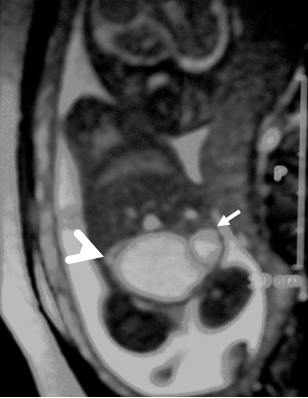

A 26-year-old pregnant women, gravida 1, para 0, was admitted to our prenatal diagnosis centre for detailed ultrasonography examination. Obstetric history was unremarkable. A single fetus was detected at 26 gestational weeks. A presacral located cystic mass measuring 45 × 55 × 40 mm was seen on ultrasound examination (Fig. 1). On doppler ultrasound, the cystic structure with both umbilical arteries around was considered an enlarged distally obstructed fetal bladder initially (Fig. 2). However, the bladder was later identified more superiorly. The amniotic fluid index was 129mm. Diagnosis of the cystic mass was unclear and a fetal MRI was performed, which delineated a large cystic mass with minimal internal echogenicity area, the type IV teratoma (big arrow head). The white arrow demonstrates a cystic mass considered as a hydrometrocolposis (Fig. 3).

In the axial plane, besides type IV SCT (big arrow head) and hydrometrocolpos (white arrow); both kidneys (white asterix) appeared in normal loca¬tion and anatomy (Fig. 4). In the coronal plane fetal bladder (black empty arrow) was noticed (Fig. 5).

Figure 3: Fetal MRI showing type IV teratoma (big arrow head) and the white arrow demonstrates hydrometrocolpos. |

Figure 4: Fetal MRI axial plane. |